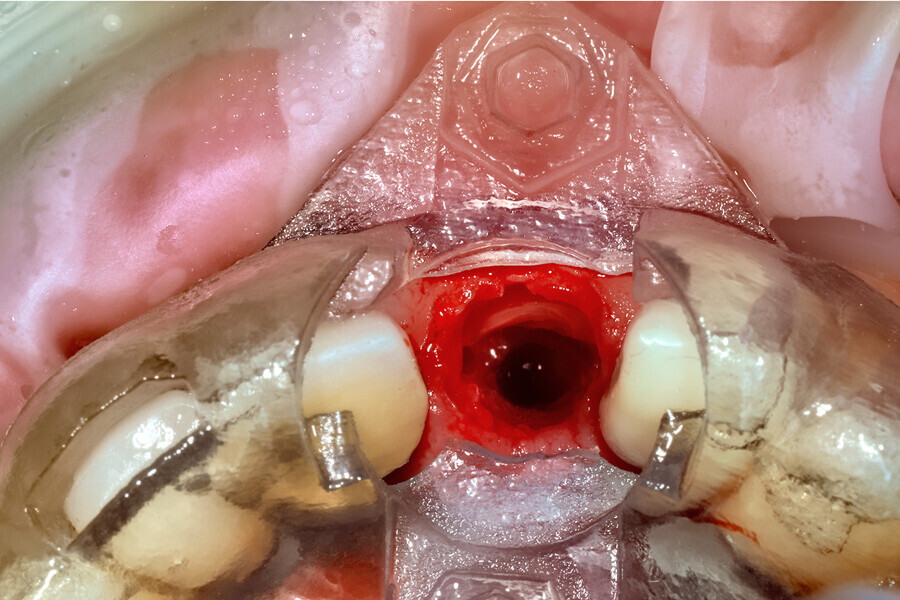

Fig. 22a: The final insert was designed to receive the guided sleeveless drills for accurate osteotomy preparation (a). The osteotomy was prepared to avoid

proximity to the remaining root fragment while leaving sufficient restorative space as previously planned (b).

Fig. 22b: The final insert was designed to receive the guided sleeveless drills for accurate osteotomy preparation (a). The osteotomy was prepared to avoid